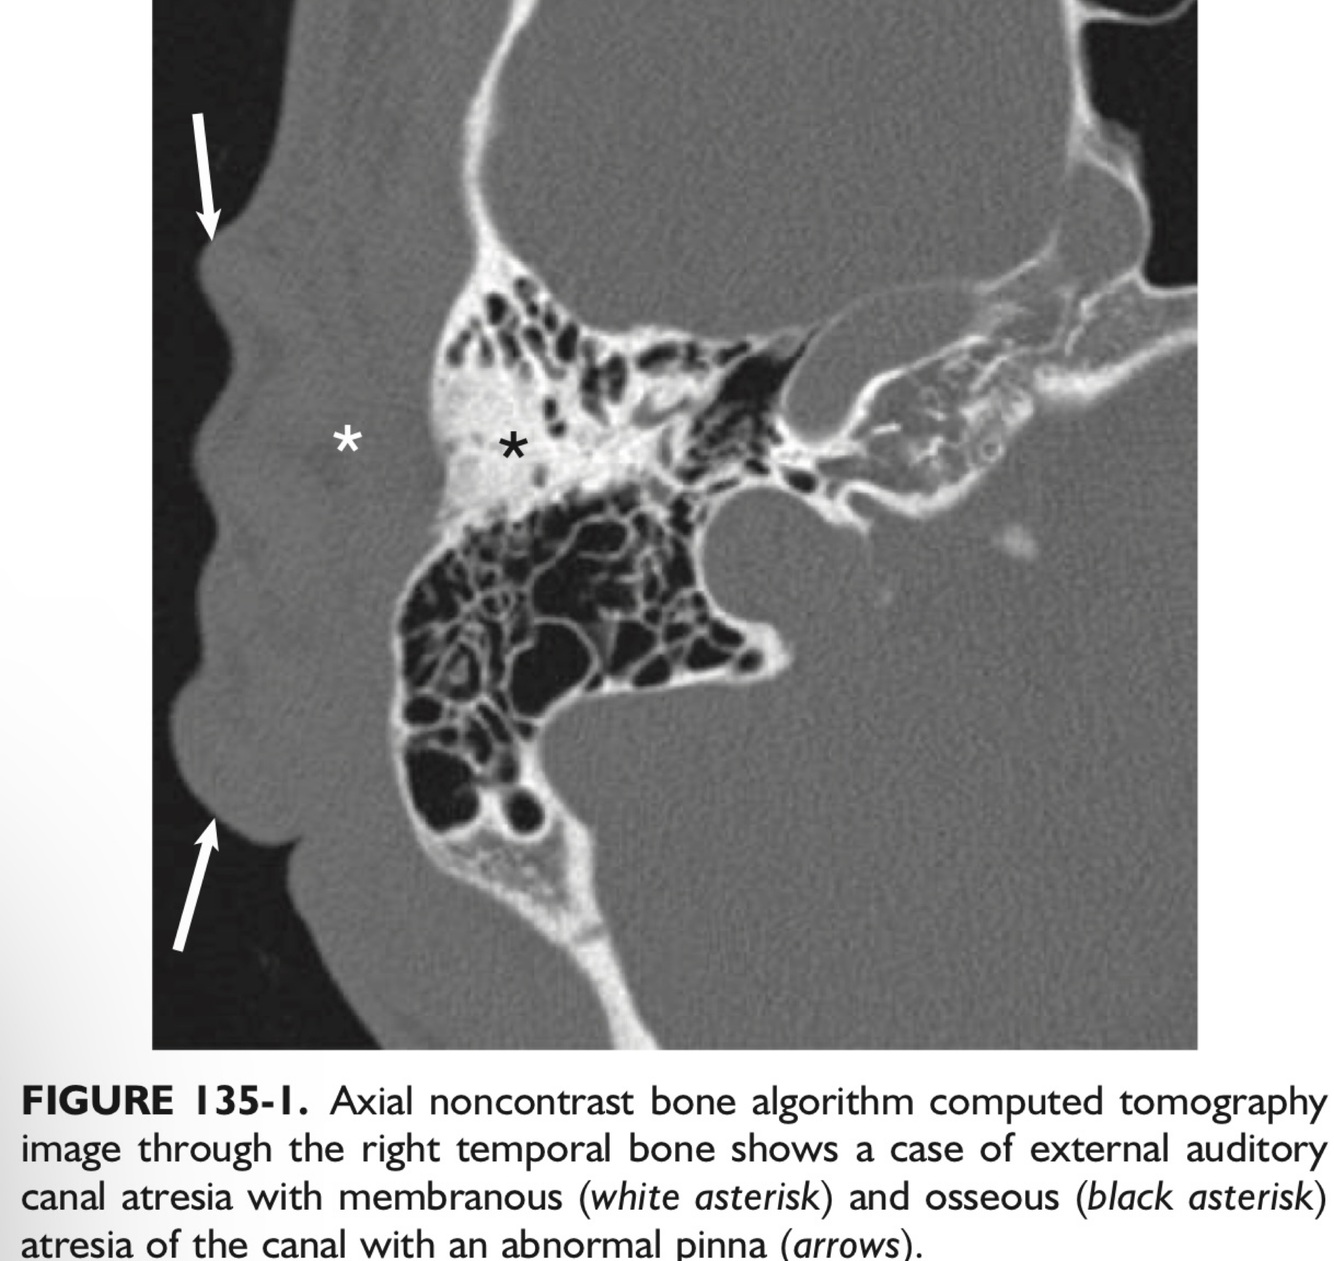

In a patient with atresia of the EAC, the FN tends to be dehiscent in the ___ segment and can overlie the ___.

In a patient with atresia of the EAC, the FN tends to be dehiscent in the tympanic segment and can overlie the oval window.